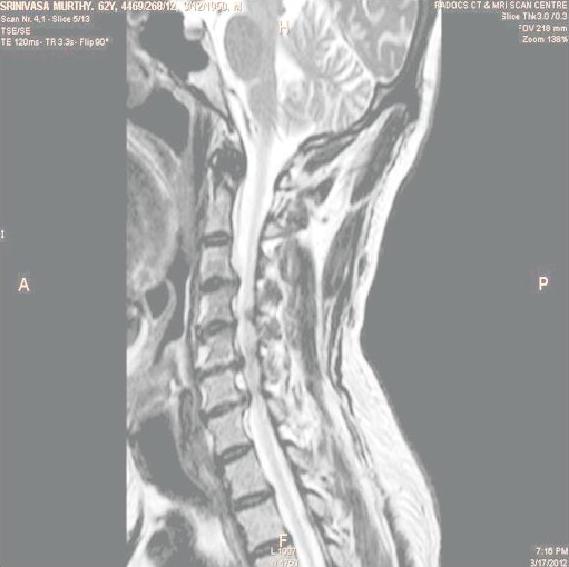

In order to show the proposed method in more detail, the algorithm is tested with other test images. The first row of Fig. 6 shows the original MRI image of thoracic spine with different views. The second row of Fig. 6 shows the same image enhanced using histogram equalization. Third row of Fig. 6 presents the MSR based enhancement scheme. Fourth row of Fig. 6 indicates Chao’s method of image enhancement. Finally, the reconstructed images using the proposed method is shown in fifth row of Fig. 6. Again, it can be seen from the results presented that the image enhancement using the proposed method is superior compared to other methods. This is evident from the image quality assessment presented in Table 1 using AWE and DWE.